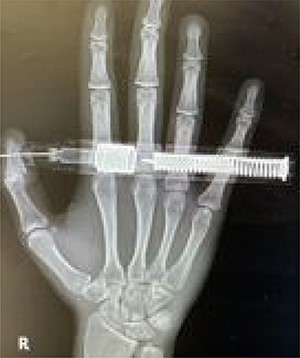

On presentation, there was no numbness or paresthesia. The accident occurred 30 min before his arrival to the ED. He accidentally injected 300 mcg of epinephrine (0.3 mg/0.3 ml, and 1:1000) into the volar pulp of his right thumb using the autoinjector. Initially, he experienced moderate pain in the right thumb, which subsided upon arrival to the ED. On examination, a puncture wound was visible on the pulp of the right thumb, distal to the interphalangeal joint. The injector needle was firmly embedded into the volar aspect of the distal phalanx of the right thumb. The digit was warm and pink in color, and the capillary refill was less than 2 s. Sensation was retained in the area distal to the puncture site. The active and passive range of motion of the thumb were intact. His vital signs and oxygen saturation were normal, and there were no signs of impaired peripheral perfusion. A hand radiography did not show a fracture of the distal phalanx of the thumb or the presence of foreign bodies (Fig. 2).

Posteroanterior view of the embedded needle on the right distal phalanx of thumb.